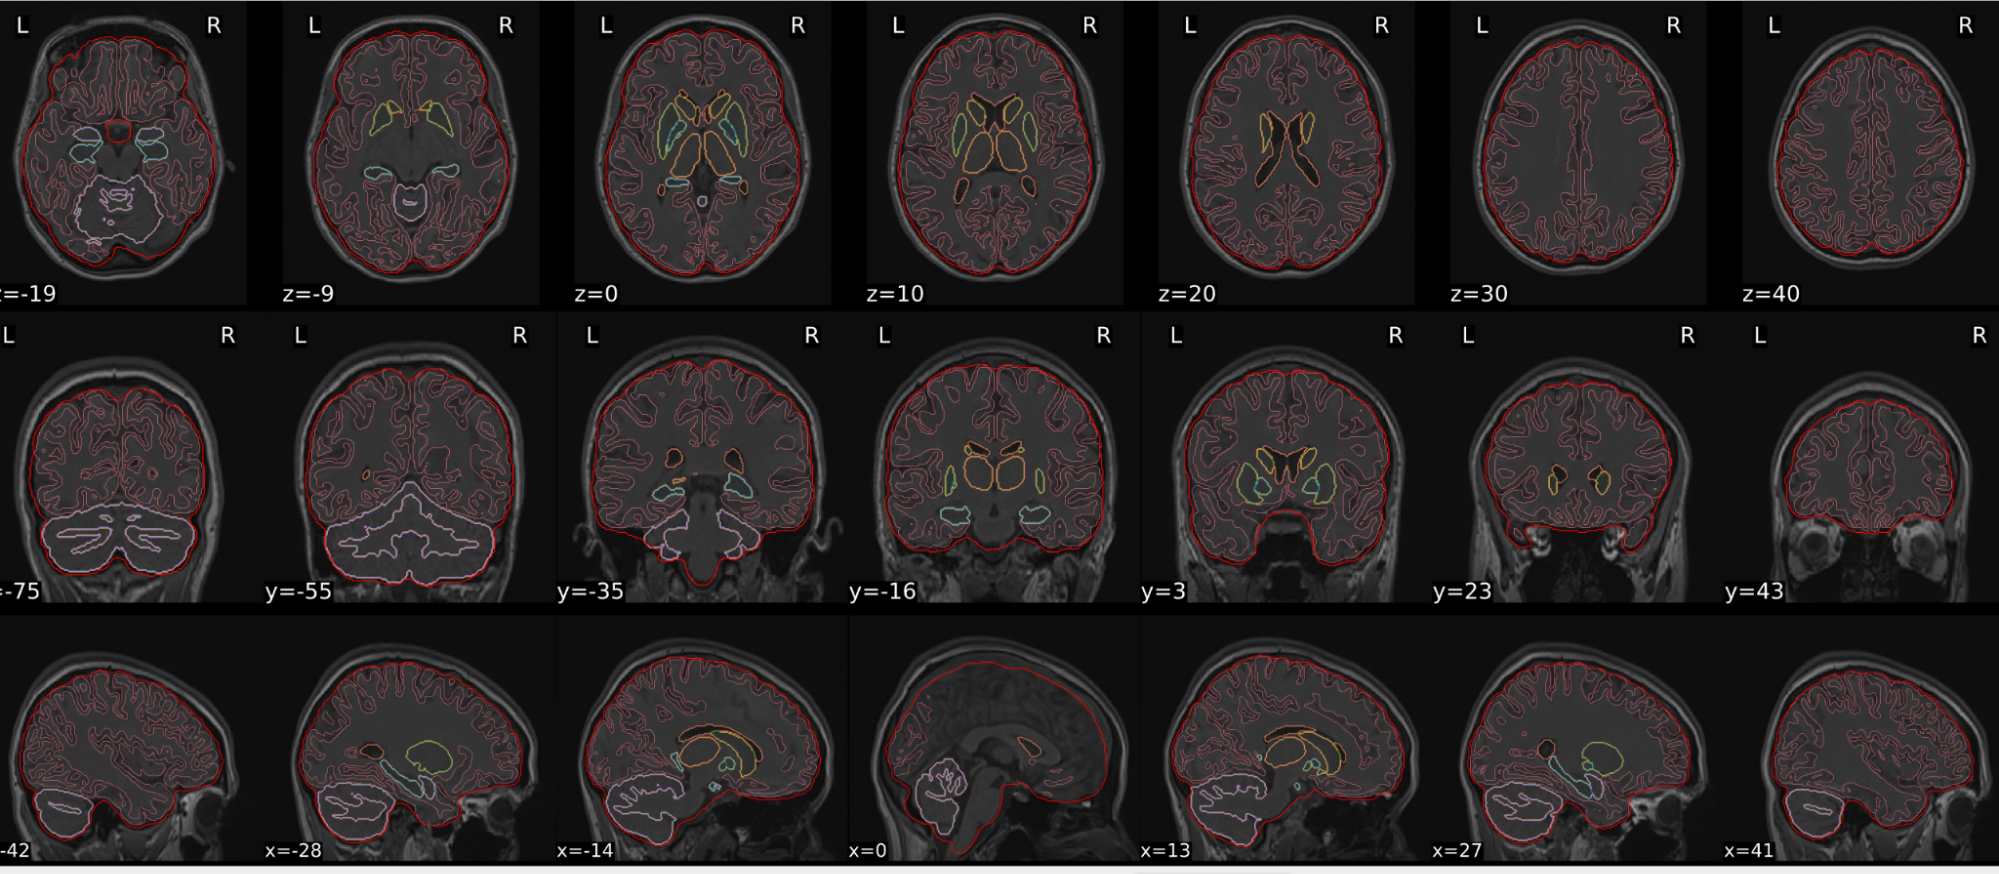

dT1w spatial normalisation

This QC step shows the registration of the T1 image to MNI space.

The registered T1 image is shown in the background with a brain atlas in MNI space as an overlay.

Example of a good subject

- If the registration performed well, you should see an overlap (i.e., correspondence of structures) between the MNI template and the T1 registered to the MNI space.

Example of a bad subject

- In case of poor registration, you should see a misalignment between the MNI template and the T1 (e.g., brain shifted down).

Summary

| good | bad |

|---|---|

| Structures of the MNI template and the registered T1 are well aligned | Structures of the MNI template and the registered T1 aren’t well aligned, e.g. brain is shifted downwards |